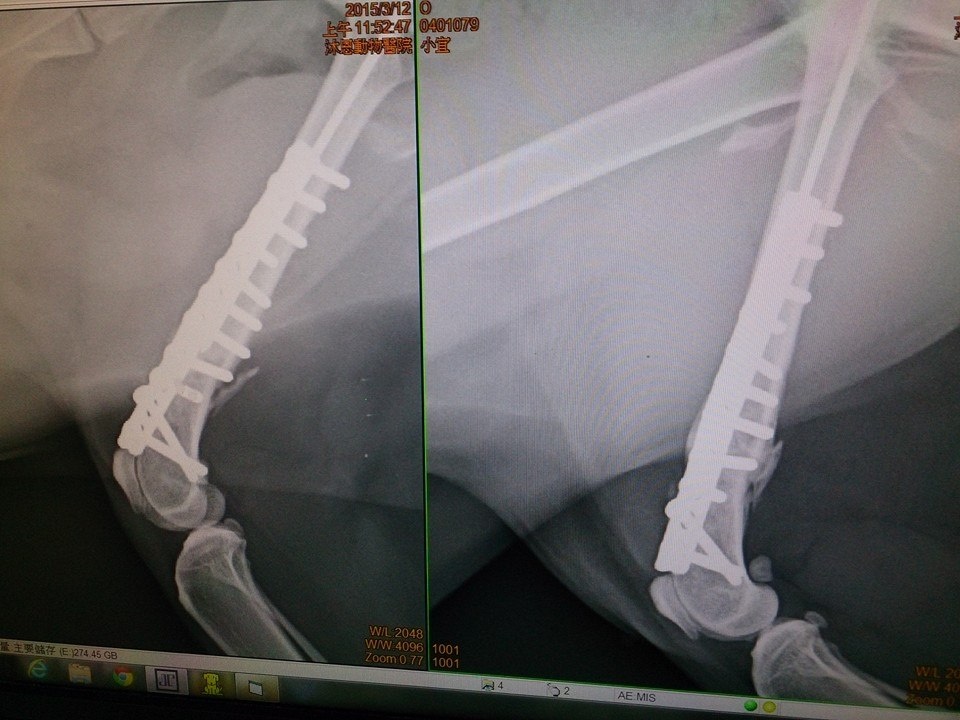

- 編號: 6044

主題: 宜蘭收容所全身撕裂傷的小宜拆骨釘 申請者姓名: 臺北市支持流浪貓絕育計劃協會 花色: 申請日期: 2015-05-26 12:34:34 申請者部落格: 申請者臉書網址: 所在縣市/合作醫院: 台北市/沐恩動物醫院 治療費用: 5400元 需求人數: 6人 已結案 (2022-04-14 17:49:36) 報名人員: Summer(已付款)、Snakek(已付款)、mimicat(已付款)、Rubyhsu(已付款)、莊子涵(已付款)、Tiffany Cheung(已付款)、 候補人員: 動物病情說明: 小宜

前後經過骨折重建術、植皮手術,

但因後腿膝蓋無法伸直並會影響到跳躍,

於2015/3/12回到協會安養之家繼續觀察後續復元情況,

2015/4月小宜回診,發現骨釘影響到發育且骨頭已經癒合進行手術拆除骨釘,小宜在大家的細心照顧下,越來越親近人,沒有那麼膽小害羞,身體也恢復健康,醫療費用還請各位幫忙。謝謝!